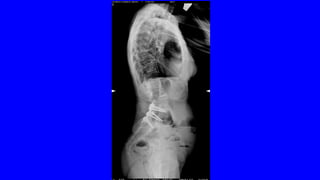

DOLOR CRÓNICO

OSTEOARTICULAR

DOLOR NOCIEPTIVO SOMÁTICO

•ES EL MÁS FRECUENTE

LA ARTROSIS